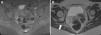

Se presenta el caso de una mujer joven con dolor ciático crónico recurrente resistente a tratamiento con medidas físicas rehabilitadoras y analgesia de tercer y cuarto escalón de la OMS. Una RM de pelvis demostró la presencia de endometriosis ciática. Tras la realización de doble anexectomía y bloqueo hormonal mejoró el cuadro clínico.

We report the case of a young woman with recurrent chronic sciatic pain refractory to treatment with physical rehabilitative measures and third and fourth step analgesia in the World Health Organization's analgesic ladder. Pelvic magnetic resonance imaging showed the presence of sciatic nerve endometriosis. The performance of double oophorectomy and hormone blockade improved the clinical picture.